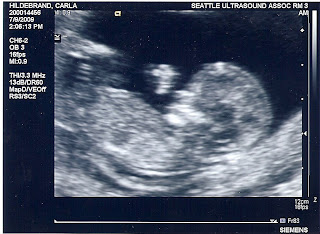

So, here is one scan: (side face profile)

and another.... (this is a face shot, see the smile)

and... last shot:

IT IS A BOY!!!!

Everything looked good. Two hands, two feet, heart activity... and LOTS OF MOVEMENT. Mr. Burns was a regular model today.

Enjoy the pictures of Mr. Burns!

Legs working out... step, step, step, step...

The hand is saying... "Yo!"

"you are tickling my feet!"

"Just relaxing... ahhhhh!"